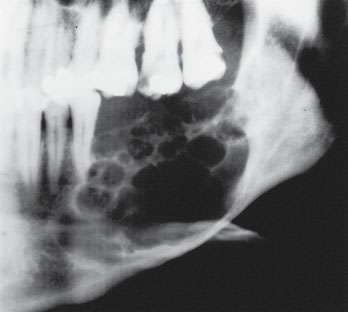

Multicystic ameloblastoma can infiltrate into the adjacent tissue and has the ability to recur and even metastasize:

• Its prevalence is a slightly older age group than the unicystic ameloblastoma.

• Radiographically, the appearance is generally unilocular or multilocular.

Fig-4-Solid-recurrent-multicystic-ameloblastoma-with-erosion-of-the-buccal-lingual079